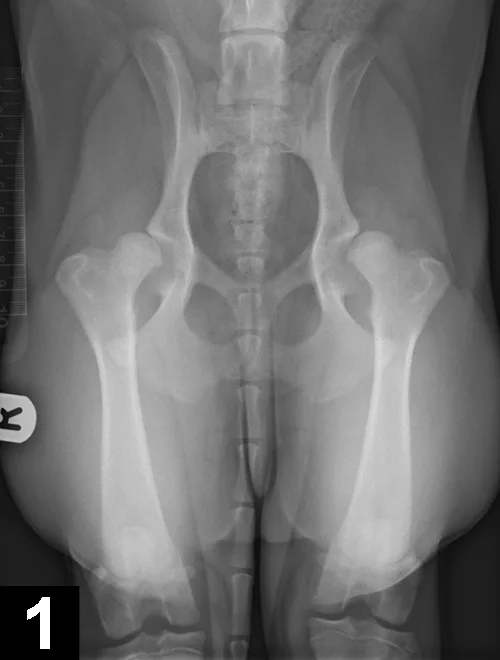

This pathology has a multifactorial etiology that affects the coxofemoral joint, most commonly in large-breed dogs (especially the German shepherd dog), but can also affect small-breed dogs and cats. Genetic and environmental factors can lead to joint laxity, which subsequently causes abnormal development of the acetabulum and femoral head, ultimately resulting in OA. Diagnosis in young patients is based on clinical signs (eg, difficulty in rising, swinging of the hindlimbs, pain, subluxation and laxity of the femoral head [Ortolani test]). Radiographic findings that confirm hip dysplasia are joint subluxation, incongruency, and early degenerative changes (Figure 1).

Figure 1. Ventrodorsal radiograph of the pelvis in a 12-month-old Labrador retriever with bunny-hopping and pain on extension of the hips. Bilateral coxofemoral subluxation and mild OA are evident.